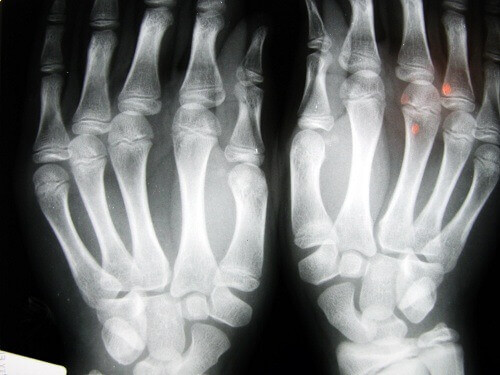

Yapılan çalışmalar sonucunda parmaklarda yumuşak doku zedelenmesi ve bir nesneyi tutmada zorluk çekme gibi deformasyon belirtileri oluştuğu keşfedildi. Bu durumun eklem bağlarının defalarca ve hızlıca esnemesi ve kasılması ile ilgili olduğu düşünülüyor.

Bu sadece eklem sağlığınızın bozulmasına yol açmakla kalmayıp kemiklerinizin aşınmasına ya da kırılmasına bile sebep olabilir. Karşılaşabileceğiniz diğer sonuçlar ise sertlik, problemli bölgede deformasyon, sadece dinlendikten sonra geçen keskin ağrılardır.

Bu problemlerin en sık görüldüğü grup 40 yaş üstü yetişkinlerdir. Eklemleri kütletme sonucu ortaya çıkan rahatsızlıklar en çok el (parmaklar ve bilekler) ve boyun bölgesinde gözlemlenir.